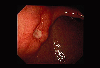

伴有明显纤维化,呈进展期癌样表现的IIc+III型早期胃癌

内窥镜